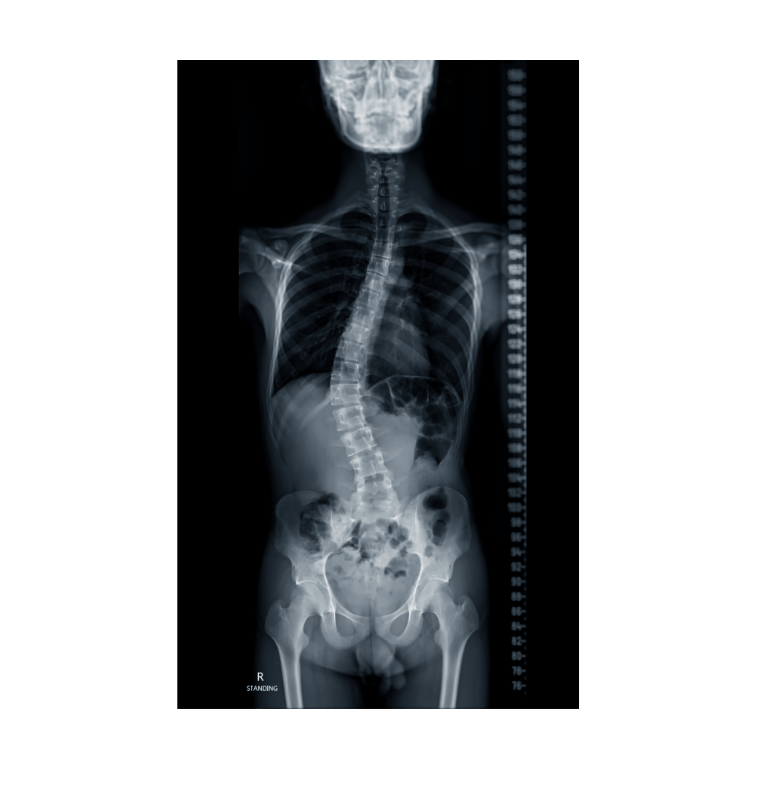

Living with scoliosis can bring challenges such as back pain, uneven posture, and limited mobility. But beyond the physical, scoliosis often affects how people feel about themselves. Changes in body shape, posture, or wearing a brace during formative years can deeply impact self-esteem and emotional health.

Yoga therapy offers a holistic, compassionate way to manage scoliosis, addressing both the body and the mind. Through mindful movement and exercises tailored to your unique curve, soft tissue release, breathwork, and self-awareness practices, you’ll not only find physical relief but also build confidence, resilience, and a deeper acceptance of your body.

Personalized practices tailored to different scoliosis patterns (C-curve, S-curve, thoracic, lumbar).